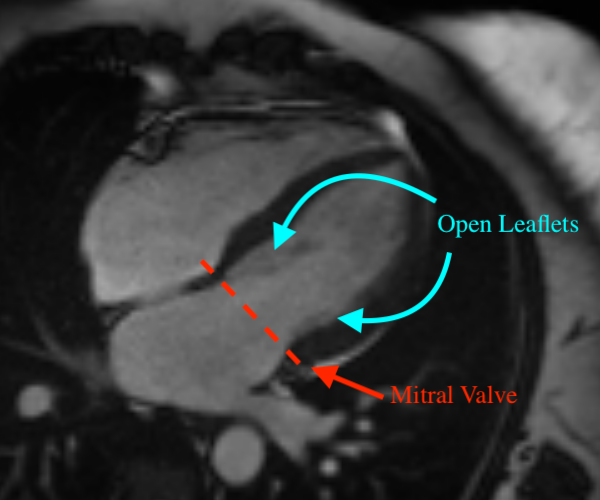

Mitral regurgitation (MR) [7] is a valvular heart disease in which the mitral valve does not close completely during systole when the left ventricle contracts, causing regurgitation – leaking of blood backwards – from the left ventricle (LV), through the mitral valve, into the left atrium (LA) – Figure 1. MR can be caused by either organic or functional mechanisms [6], with organic MR leading to atrial and annular enlargement and functional MR increasing atrial pressure. As MR progresses, it may cause arrhythmia, shortness of breath, heart palpitations and pulmonary hypertension [14]. Left undiagnosed and untreated, MR may cause significant hemodynamic instability and congestive heart failure which can lead to death [17], while acute MR usually necessitates immediate medical intervention [22]. Thus, early detection and assessment of MR are crucial for optimal treatment outcomes, with the best short-term and long-term results obtained in asymptomatic patients operated on in advanced repair centers with low operative mortality (<1%absentpercent1<1\%) and high repair rates (8090%absent80percent90\geq 80-90\%[7].

Figure 1: Three cardiovascular magnetic resonance (CMR) images showing the long-axis four-chamber view of the heart. Left: a heart with normal mitral valve. Middle: a heart with normal mitral valve when the valve leaflets are open. Right: a heart with mitral regurgitation. The red dotted line denotes the mitral valve.